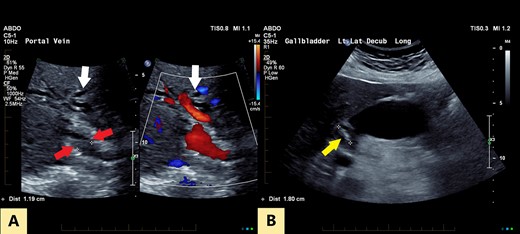

An ultrasound of the abdomen revealed a large gallstone in the gallbladder neck measuring 36 mm with mild biliary dilatation (Fig. 1). Magnetic resonance cholangiopancreatography (MRCP) revealed an irregular long stricture of the extrahepatic bile duct beginning distal to the primary biliary confluence, involving the common hepatic duct for a distance of 20 mm (Fig. 2). A multiphase liver magnetic resonance imaging was performed which confirmed a malignant appearing stricture of the common hepatic duct and showed an ill-defined soft tissue lesion in the porta hepatis between the gallbladder neck and the common hepatic duct (Fig. 3). Her Ca 19.9 was 160 kU/L (ref range < 35 kU/L).

2D projectional MRCP reveals abrupt segmental stricture (red arrow) of the common hepatic duct with marked intrahepatic biliary dilation. Gall bladder is distended and there is a calculus (yellow arrow) in the gall bladder neck.